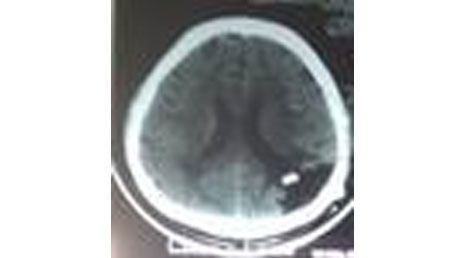

6. Arachnoid cyst